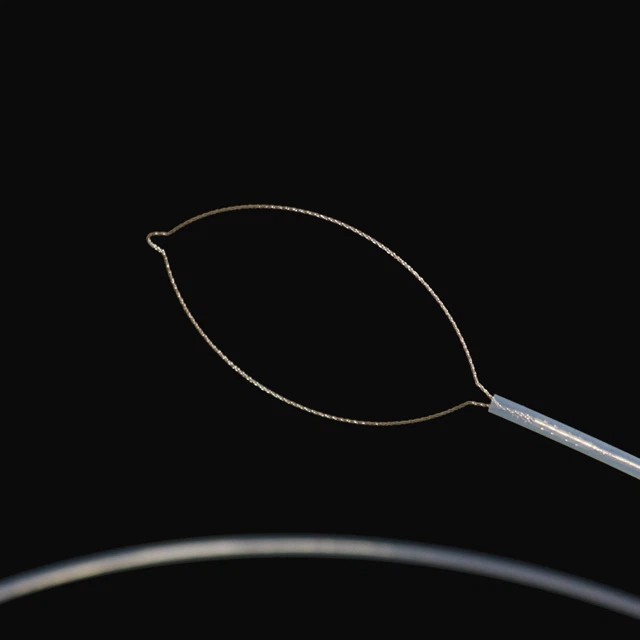

മൊത്തം തരം

FG -28 u -25 d2 |

വലയുമായി ഓവൽ |

|

FG -28 u -30 d2 |

30 |

വലയുമായി ഓവൽ |